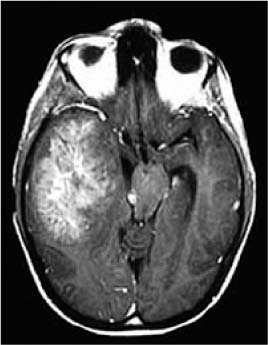

wallpapers Benign Brain Tumor Surgery Recovery early postoperative seizures eps in patients undergoing brain tumour surgery scientific reports

• Early Postoperative Seizures Eps In ... | 2006x693 px